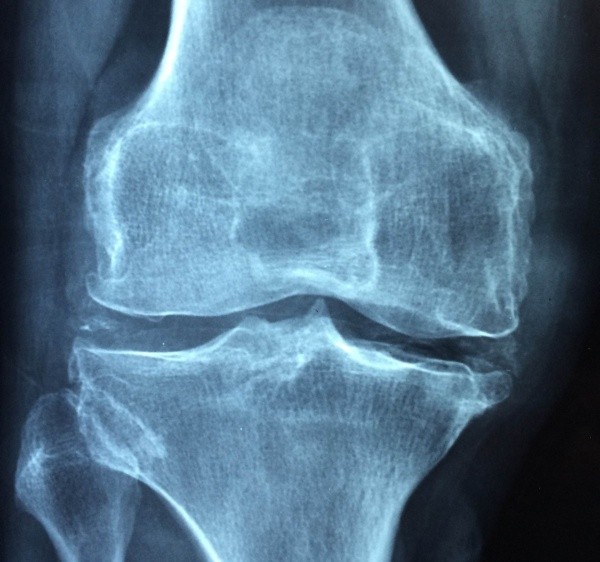

Эксперты из США во главе с Салах-Уддином Ахмедом изучили группу синовиальных фибропластов, выстилающих суставы. При ревматоидном артрите в таких клетках воспаление запускает TNF-альфа.

Ученые удалили белок сульфатаза-2 и наблюдали поведение клеток при стимуляции TNF-альфа. В результате, при удаленном белке воспаление было не такое сильное.